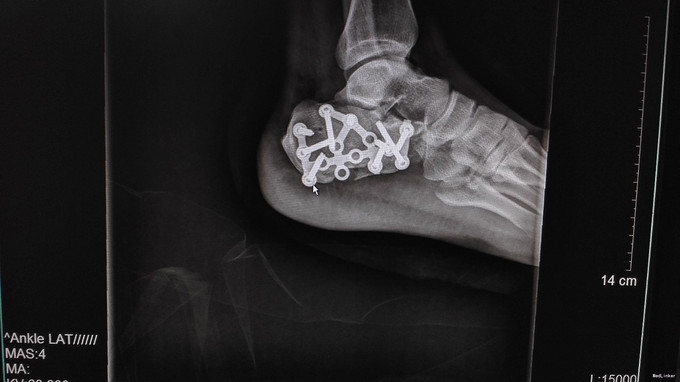

左足跟淤血肿胀明显,无明显畸形,皮肤完整,局部压痛明显,可扪及骨擦感,纵向叩击痛阳性,足趾活动正常,末梢血运、感觉正常。左跟骨X片示:左跟骨粉碎性骨折,左足部CT示:左侧跟骨粉碎性骨折,累及跟距关节面。

左跟骨粉碎性骨折,排除手术禁忌症后行左跟骨粉碎性骨折切开复位内固定术。

中年男性患者,因“跌倒致左足跟部疼痛、活动受限4小时”入院,左跟骨X片及左足部CT提示:左跟骨粉碎性骨折,累及跟距关节面。结合临床症状、体征及影像学检查,诊断左跟骨粉碎性骨折,且累及关节面,手术指征明确,排除手术禁忌后行切开复位内固定术,术后复查X片示对位良好。出院1月后复查,1月内避免负重。